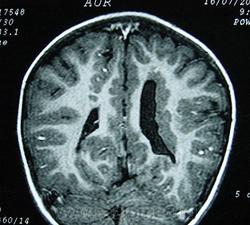

Гетеротопии. Перивентрикулярная гетеротопия. Субэпендимальная нодулярная (узелковая) гетеротопия.

Наиболее частым вариантом миграционных нарушений является гетеротопия - скопление нейронов, остановившихся в различных аномальных местах на пути следования к коре головного мозга. Такая остановка происходит не позже 5-го месяца внутриутробного развития. Изолированный участок узловатой массы называется «гетеротопион». В настоящее время описаны следующие варианты гетеротопии:

Перивентрикулярная субэпендимальная гетеротопия